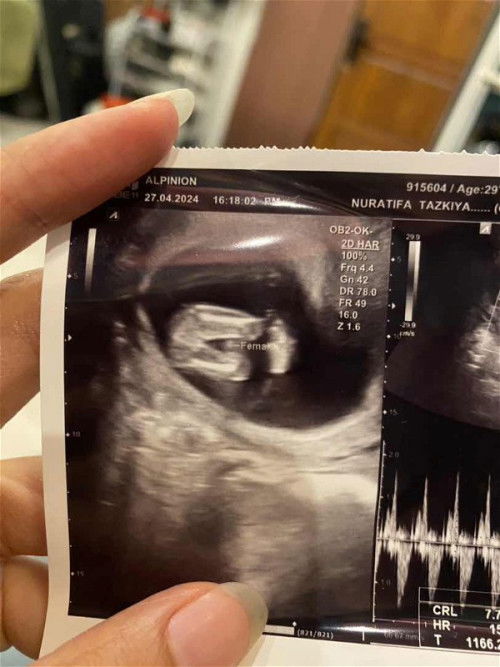

Sharing usg gender baby

Hai bunda2 semoga sehat selalu. Ini hasil usg 13w6d saya diperkirakan bakal baby girl karna ga ada perkututnya atau apa blm tumbuh ya?😄 bunda2 disini gmn pengalaman mengetahui gender babynya?